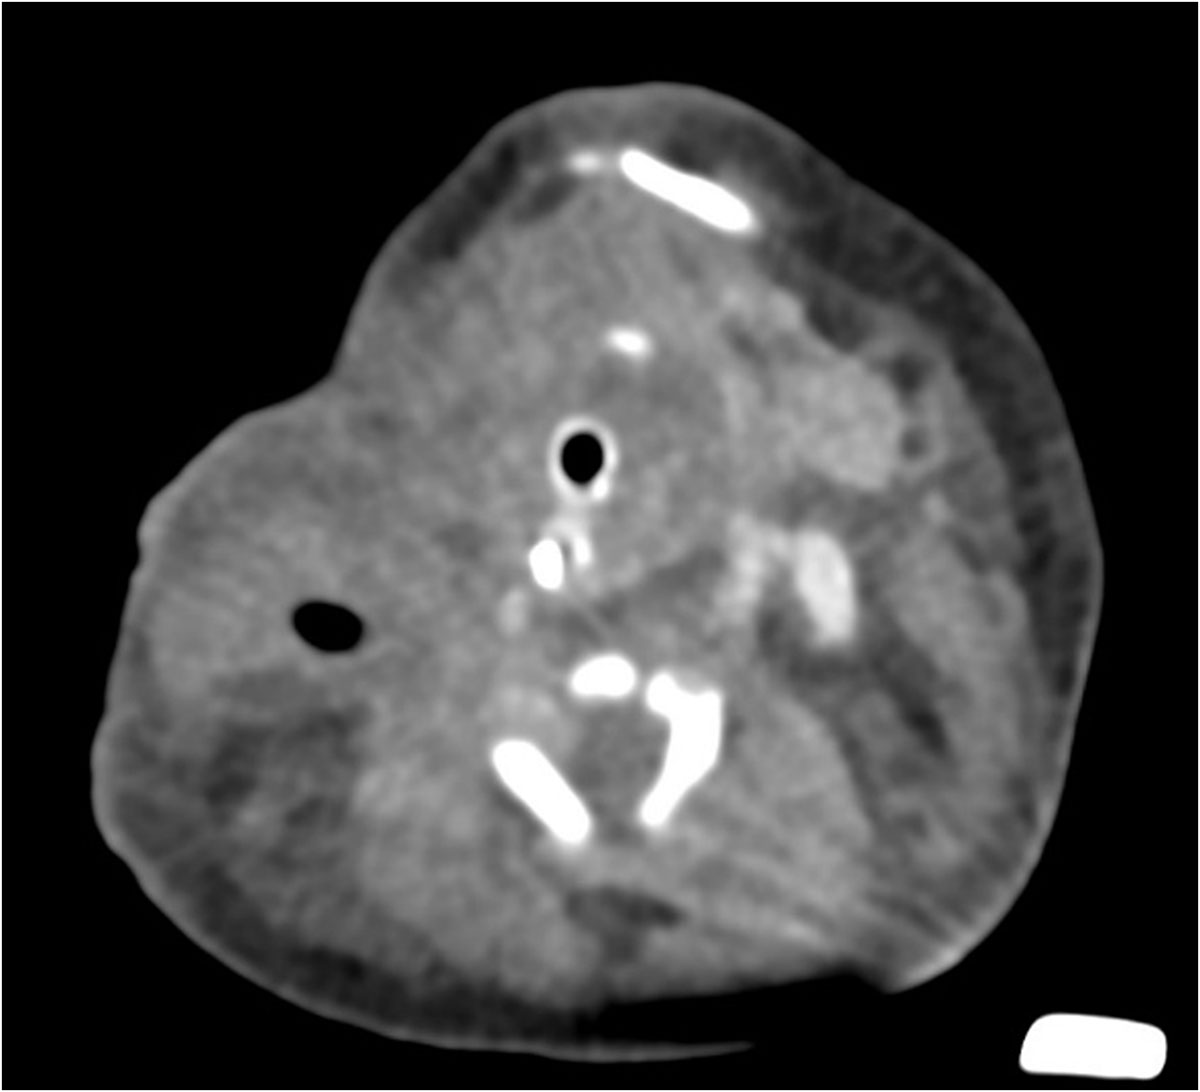

Se identifica imagen redondeada, de bordes lobulados, dependiente de tejidos blandos, heterogénea por áreas sólidas y quísticas internas, así como algunas calcificaciones irregulares dispersas, tras la aplicación de medio de contraste con realce ávido heterogéneo en sus porciones sólidas, con dimensiones de 89.3×88.3×80.9 mm y volumen de 333.6 cc; localizada en los espacios masticador, parotídeo, parafaríngeo, submandibular, visceral, supraesternal, perivertebral bucal y cervical posterior derechos.5. IMÁGENES

La tomografía computarizada (TC) muestra una masa compleja bien delimitada, con componentes sólidos, quísticos, calcificados y grasos, hallazgo característico de los teratomas maduros. La TC permite valorar la relación con estructuras vasculares, la vía aérea y el mediastino, siendo útil en la planificación quirúrgica.

El teratoma cervical es una neoplasia congénita rara, derivada de células germinales pluripotenciales que contienen tejidos de las tres capas embrionarias. Representa menos del 5% de los teratomas pediátricos y su localización en el cuello puede ocasionar compromiso de la vía aérea, constituyendo una urgencia neonatal potencialmente mortal.